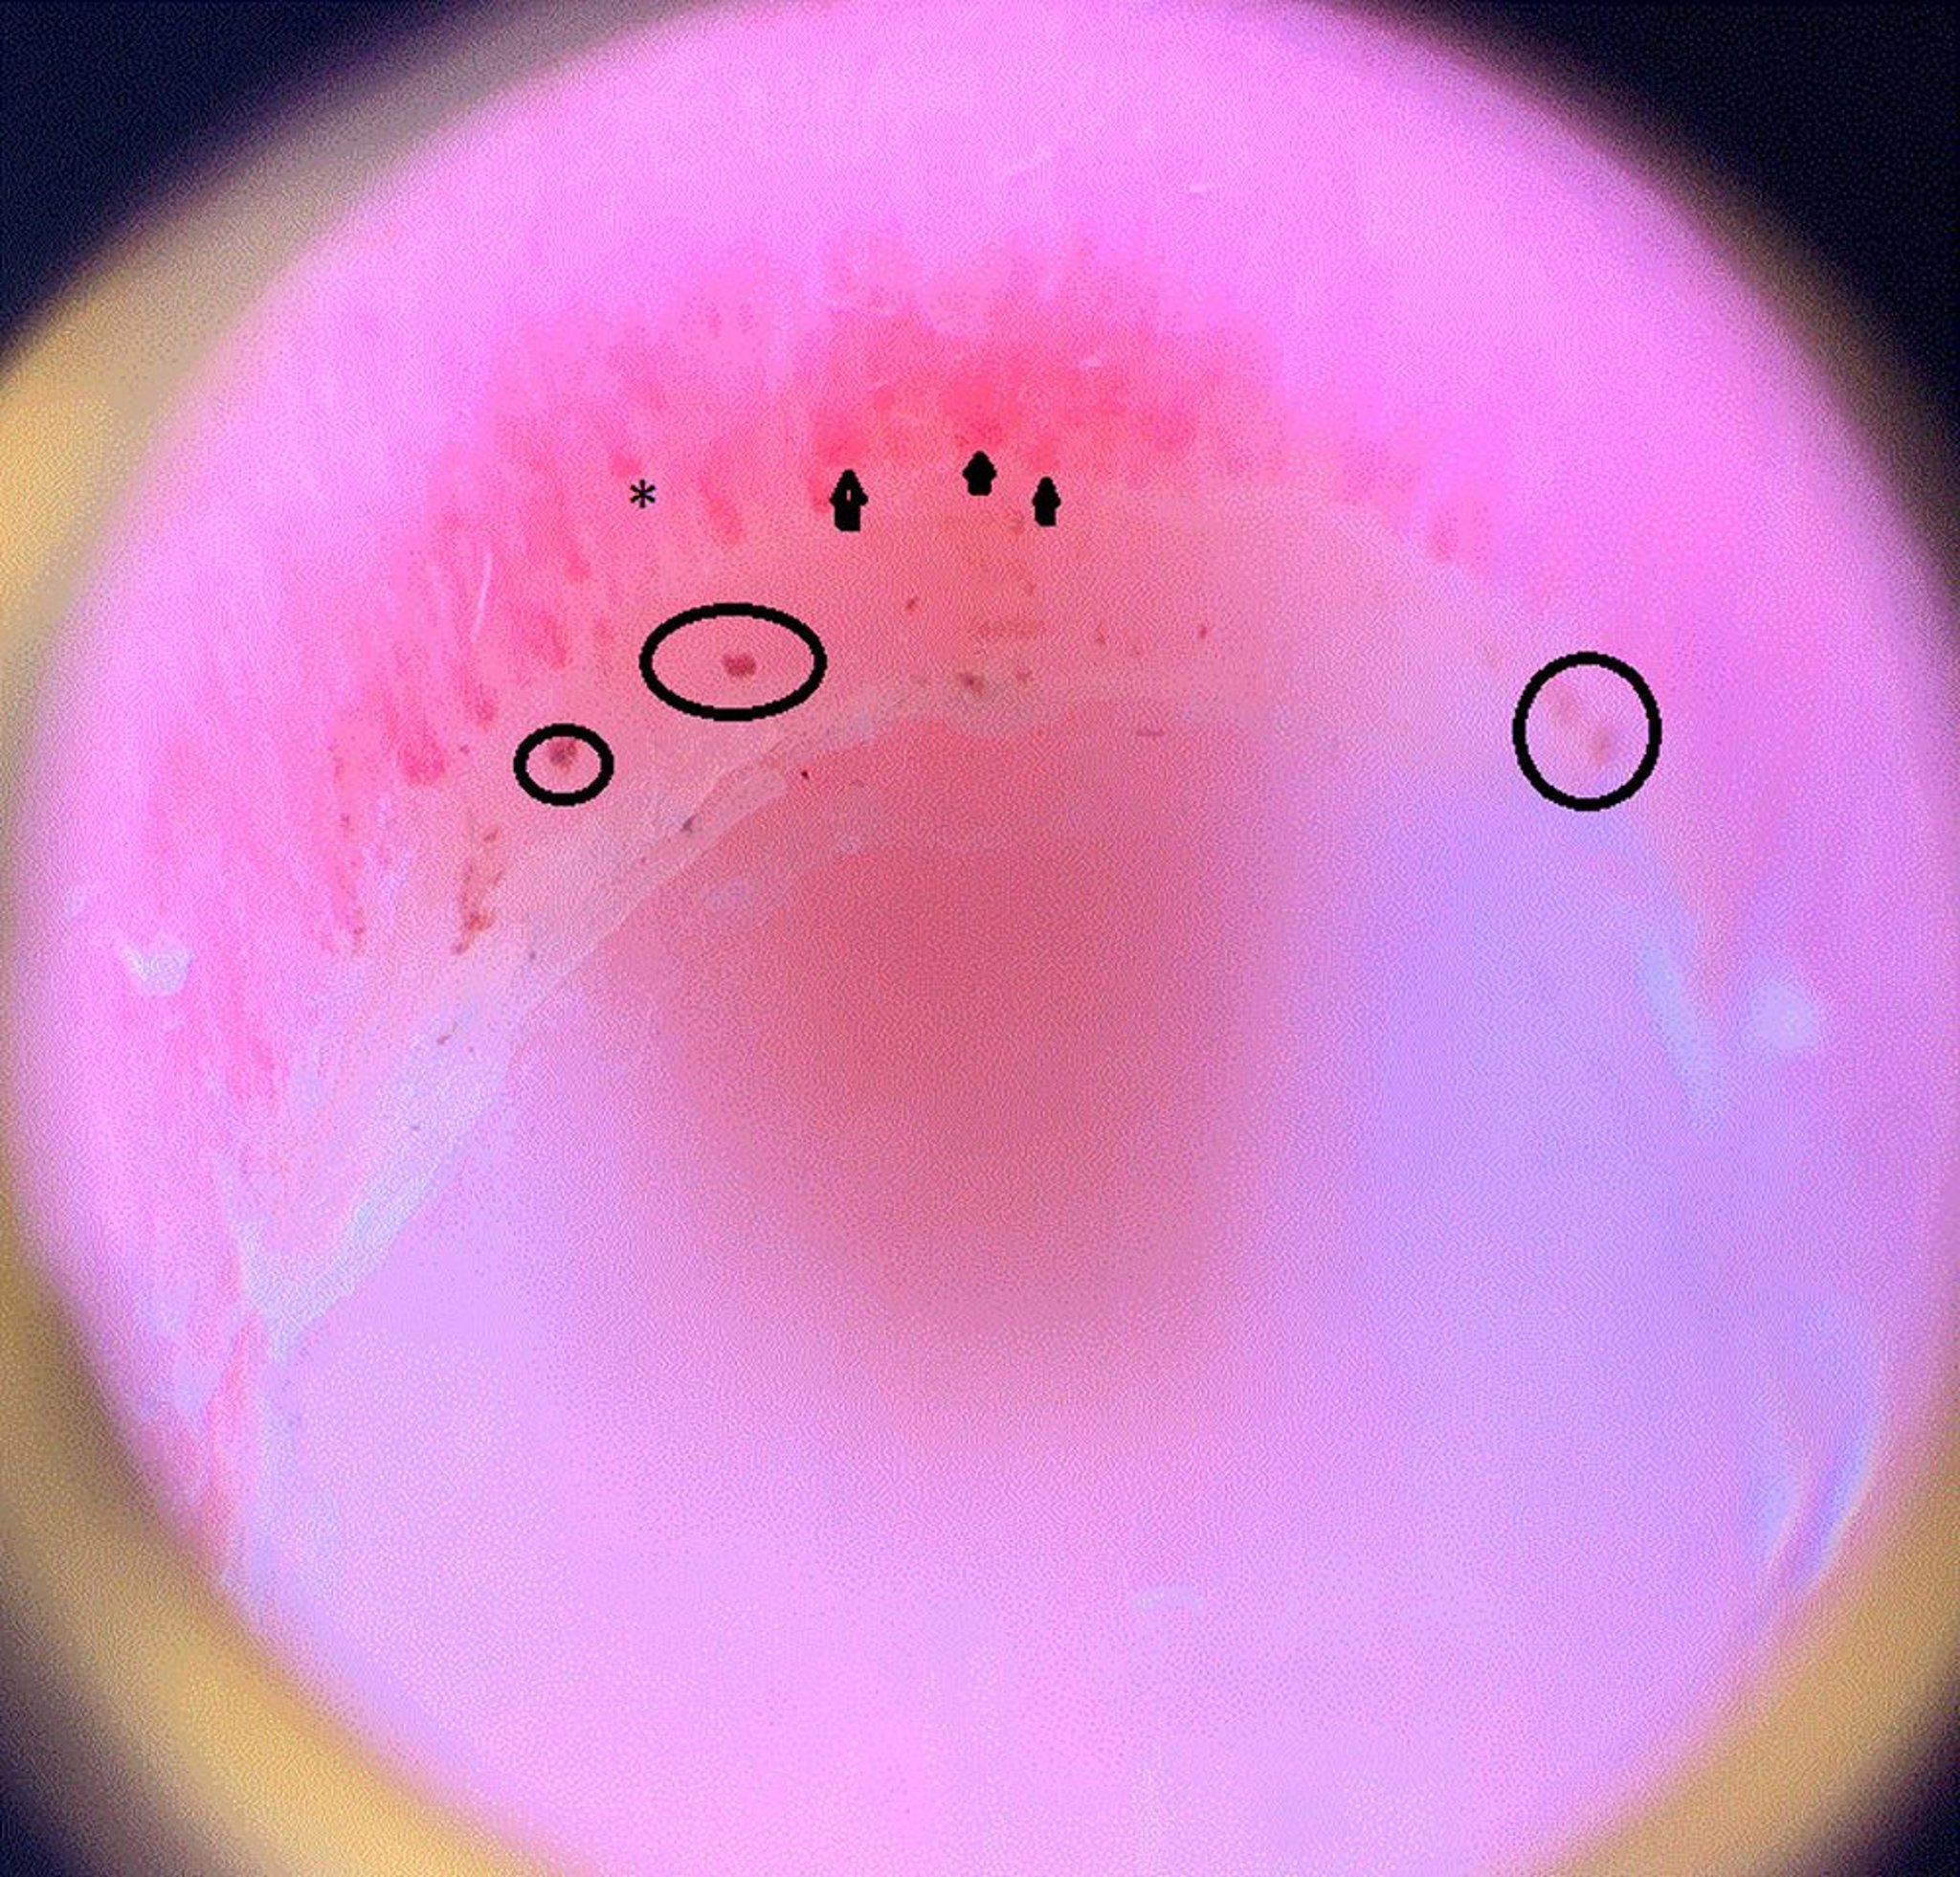

Capillaroscopie

Cette image montre des anses capillaires dilatées (pointes de flèches), une zone de décrochage, ce qui signifie que le capillaire se termine prématurément et semble donc plus court que les autres (astérisque), ainsi que des hémorragies périunguales (cercles) dans le pli d'un ongle d'un patient atteint de sclérodermie.

Image courtoisie de Sanjeev Patil, MD.